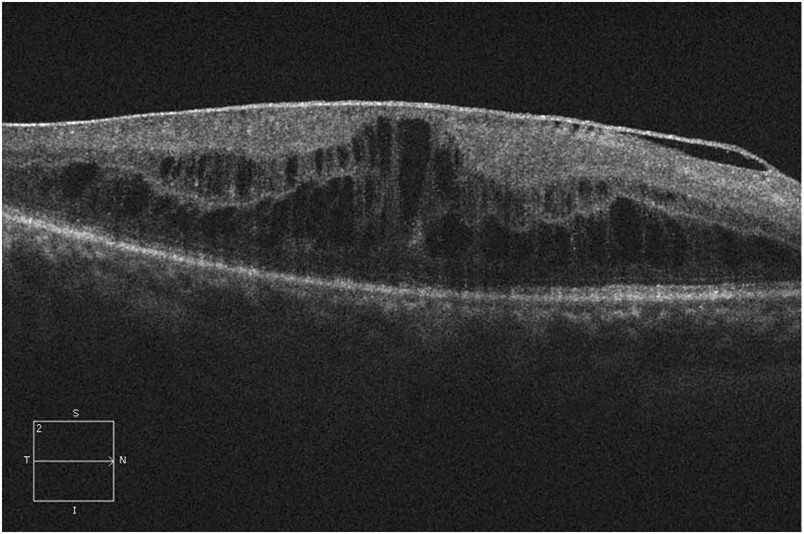

Dense epiretinal membrane overlying the retinal surface, with an elevated foveal contour and significant intraretinal cystic spaces in a patient with diabetes. Published online with permission from the AAO.